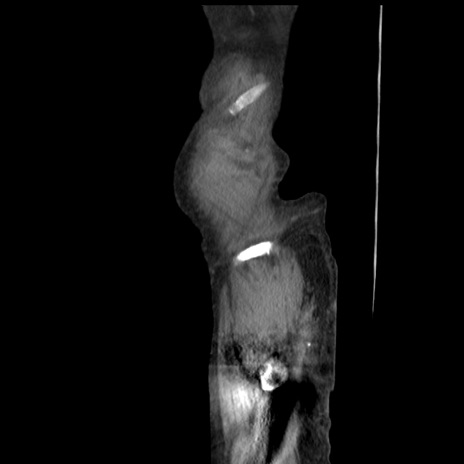

冠状断像